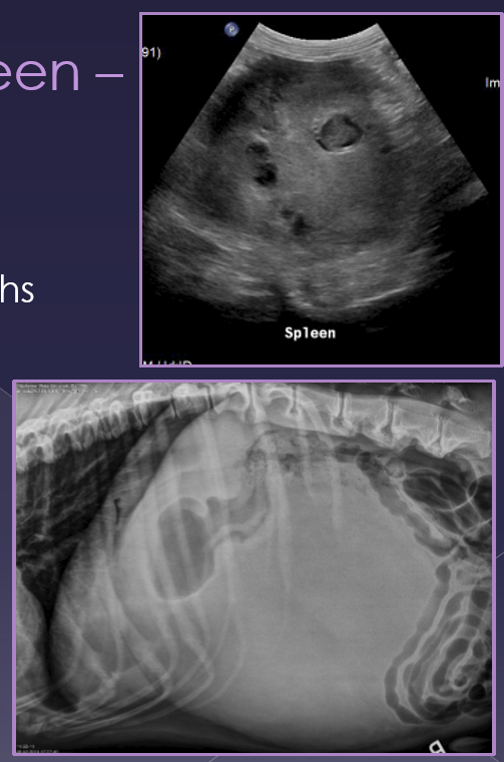

splenic torsion

spleen twists on its vascular pedicle

large breed dogs

uncommon

acute

shock, anorexia, vomiting, diarrhea, abdominal pain, enlarged spleen

chronic

anorexia, vomiting, diarrhea, abdominal pain, enlarged spleen, hemoglobinuria

radiographs

abnormal location

mass effect

gas bubbles

comma-shaped

ultrasound

variable echotexture

dilated vessels - gas bubbles

thrombi

Neoplasia of the spleen

benign or malignant

very common

large breed dogs » small breed dogs

shock, enlarged abdomen, abdominal mass, fluid wave, lethargic, vomiting, abdominal pain

same as acute but episodic presentation

diagnosis

abdominal radiographs

mass-effect

peritoneal effusion

thoracic radiographs

metastasis

mixed echotexture

cavitated lesions

enlarged spleen